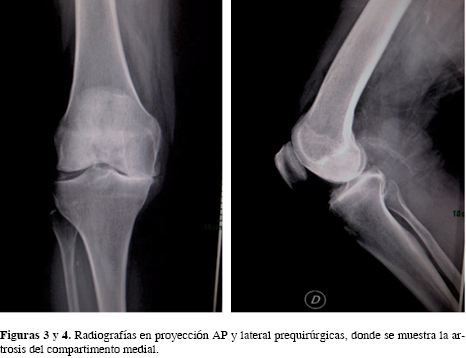

Se incluyeron todos los pacientes intervenidos de AUR con diagnóstico de gonartrosis del compartimento medial. El tamaño de la muestra que se seleccionó fue de 25 pacientes (30 rodillas) sometidos a AUR en el Instituto Nacional de Ciencias Médicas y Nutrición "Salvador Zubirán", de Enero del 2002 a Septiembre de 2013. Los criterios de inclusión para una AUR fueron los siguientes: pacientes con osteoartrosis o necrosis avascular del compartimento medial de la rodilla (Figuras 1 y 2), dolor medial, deformidad en varo corregible menor de 15o, estabilidad anteroposterior con integridad del ligamento cruzado anterior y posterior, espacio articular lateral sin evidencia de lesiones degenerativas en las radiografías AP con apoyo; radiografías anteroposterior (AP) con apoyo, lateral (Figuras 3 y 4) y con estrés en valgo y varo para corroborar corrección de la deformidad (Figura 5). Los criterios de exclusión fueron los pacientes que a pesar de contar con gonartrosis medial fueron sometidos a artroplastía total de rodilla (ATR). La edad, peso y lesión en el cartílago patelofemoral no fueron causa de exclusión.